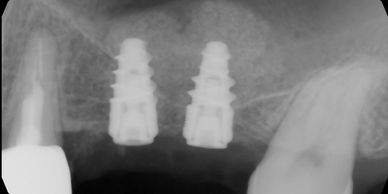

Having missing teeth, dental implants are the best solutions in most cases. Dental implants are strong, allowing patients to eat like having natural teeth. Better yet, dental implants and crowns are made of titanium and porcelain, so they will not get decayed.

Dental implant with bone graft. Sometimes, after losing teeth for a long time, jawbone will shrink, making it impossible to place implants. Many bone grafting techniques help the body to grow bone to support dental implants.